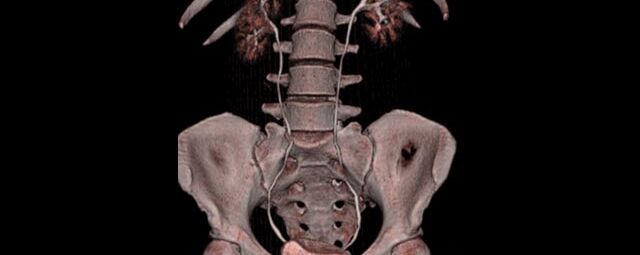

Unser neuer Canon-Computertomograph Aquilion Lightning SP

Seit August 2019 arbeiten wir am Standort Schönefeld mit einem hochmodernen 80-Zeilen-CT der Firma Canon.

Ganz auf Patientensicherheit ausgelegt werden mit diesem CT individuell für jeden Patienten automatisch Strahlendosis und Kontrastmittelmenge reduziert und gleichzeitig bestmöglicher Bildkontrast und eine hohe Detailauflösung erreicht.

Spezielle Software ermöglicht jetzt zum Beispiel:

• verbesserte Bildqualität bei Patienten mit Implantaten (z. Bsp. Hüftendoprothesen)

• besonders hochauflösende, strahlendosissparende Darstellung aller Skelettstrukturen

• mehrdimensionale Darstellung vasculärer Strukturen mit zahlreichen Auswertungstools